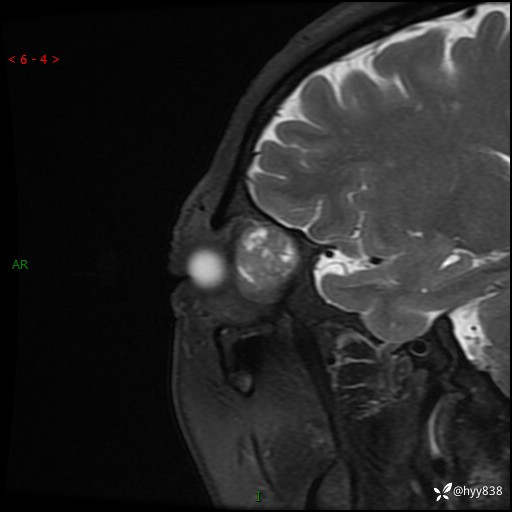

老年女性,右眼球突出1月。说说鉴别诊断,看谁第一个秒---(有结果)

主诉:发现右眼球突出1月余

简要病史:患者于1月前无明显诱因发现右眼球突出,偶感磨痛、眼胀,无视力下降,无头痛,恶心呕吐等不适。10天前就诊于当地县人民医院就诊,完善头颅ct检查,诊断为右侧眼眶肿物,建议患者上级医院进一步治疗,患者因个人原因拒绝。拟行手术,来我院就诊,门诊行相关检查后以“右眼眼眶肿物”收入院。 患病以来,患者精神饮食睡眠尚可,大小便如常、体重无明显改变。

辅助检查:MRI

临床诊断:眼眶肿物

眼眶MRI平扫+增强